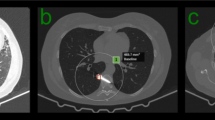

Here, \(\beta \) is a coded contrast-offset-invariant relation between the seven signals; \(\mathbb {B}_7\) denotes the set of codes for the possible ordinal 7-signal relations; \(F_{7:\rho }\left( {\mathrm {g}}^o\right) \) is an empirical marginal probability of the code \(\beta \) ; \(\beta \in \mathbb {B}_7\), over all the 7-voxel congurations with the center-to-voxel distance \(\rho \) in \(\mathrm {g}^o\), and \(F_{7:\rho :core}\left( \beta \right) \) is the like probability for the core distribution. The computed energy is used as a descriptive feature to discriminate between the malignant and benign nodules (Fig. 3).

A sample of benign (rst) and malignant (second-row) nodules (a), their 3D visualization of HU values (b), and their Gibbs energy which shows high energy for (brighter) for benign and less energy for malignant (darker) (c). The figure was created in MATLAB R2018B (https://www.mathworks.com/products/matlab.html).